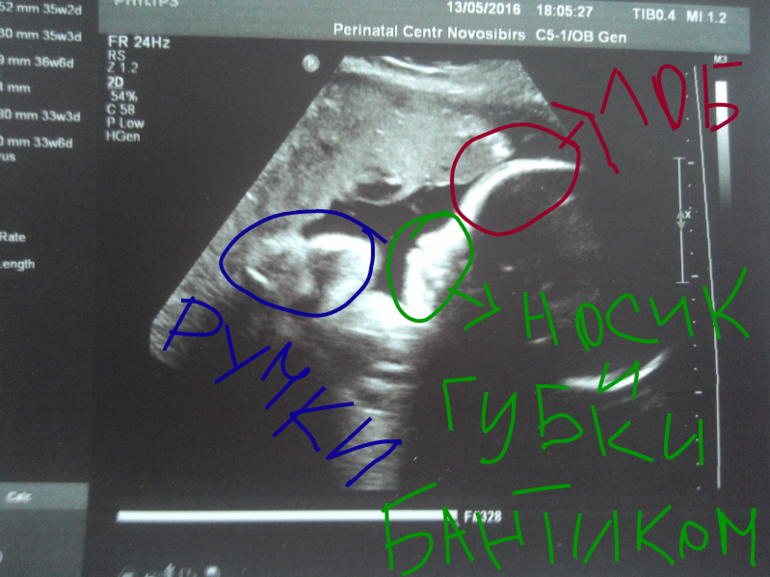

Ну и вот фото с узи))